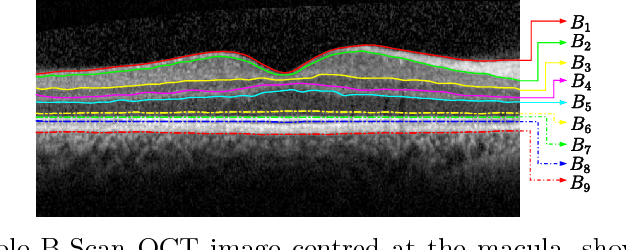

Abstract:In this paper, we propose a novel retinal layer boundary model for segmentation of optical coherence tomography (OCT) images. The retinal layer boundary model consists of 9 open parametric contours representing the 9 retinal layers in OCT images. An intensity-based Mumford-Shah (MS) variational functional is first defined to evolve the retinal layer boundary model to segment the 9 layers simultaneously. By making use of the normals of open parametric contours, we construct equal sized adjacent narrowbands that are divided by each contour. Regional information in each narrowband can thus be integrated into the MS energy functional such that its optimisation is robust against different initialisations. A statistical prior is also imposed on the shape of the segmented parametric contours for the functional. As such, by minimising the MS energy functional the parametric contours can be driven towards the true boundaries of retinal layers, while the similarity of the contours with respect to training OCT shapes is preserved. Experimental results on real OCT images demonstrate that the method is accurate and robust to low quality OCT images with low contrast and high-level speckle noise, and it outperforms the recent geodesic distance based method for segmenting 9 layers of the retina in OCT images.

Abstract:Optical coherence tomography (OCT) is a non-invasive imaging technique that can produce images of the eye at the microscopic level. OCT image segmentation to localise retinal layer boundaries is a fundamental procedure for diagnosing and monitoring the progression of retinal and optical nerve disorders. In this paper, we introduce a novel and accurate geodesic distance method (GDM) for OCT segmentation of both healthy and pathological images in either two- or three-dimensional spaces. The method uses a weighted geodesic distance by an exponential function, taking into account both horizontal and vertical intensity variations. The weighted geodesic distance is efficiently calculated from an Eikonal equation via the fast sweeping method. The segmentation is then realised by solving an ordinary differential equation with the geodesic distance. The results of the GDM are compared with manually segmented retinal layer boundaries/surfaces. Extensive experiments demonstrate that the proposed GDM is robust to complex retinal structures with large curvatures and irregularities and it outperforms the parametric active contour algorithm as well as the graph theoretic based approaches for delineating the retinal layers in both healthy and pathological images.